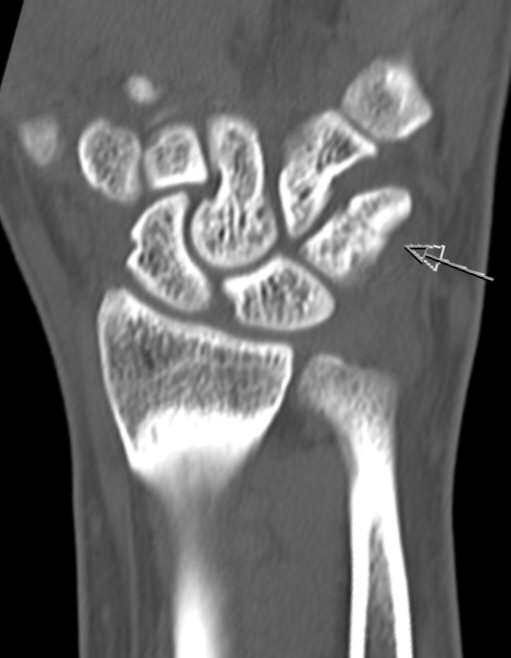

Skada: Fraktur triquetrium

- Korpusfraktur

Odislocerad fraktur i korpus, behandlades med dorsal gipsskena i 4 veckor.

- Kartlägg med DT

- Ofta liten felställning, kan då behandlas med gipsimmobilisering